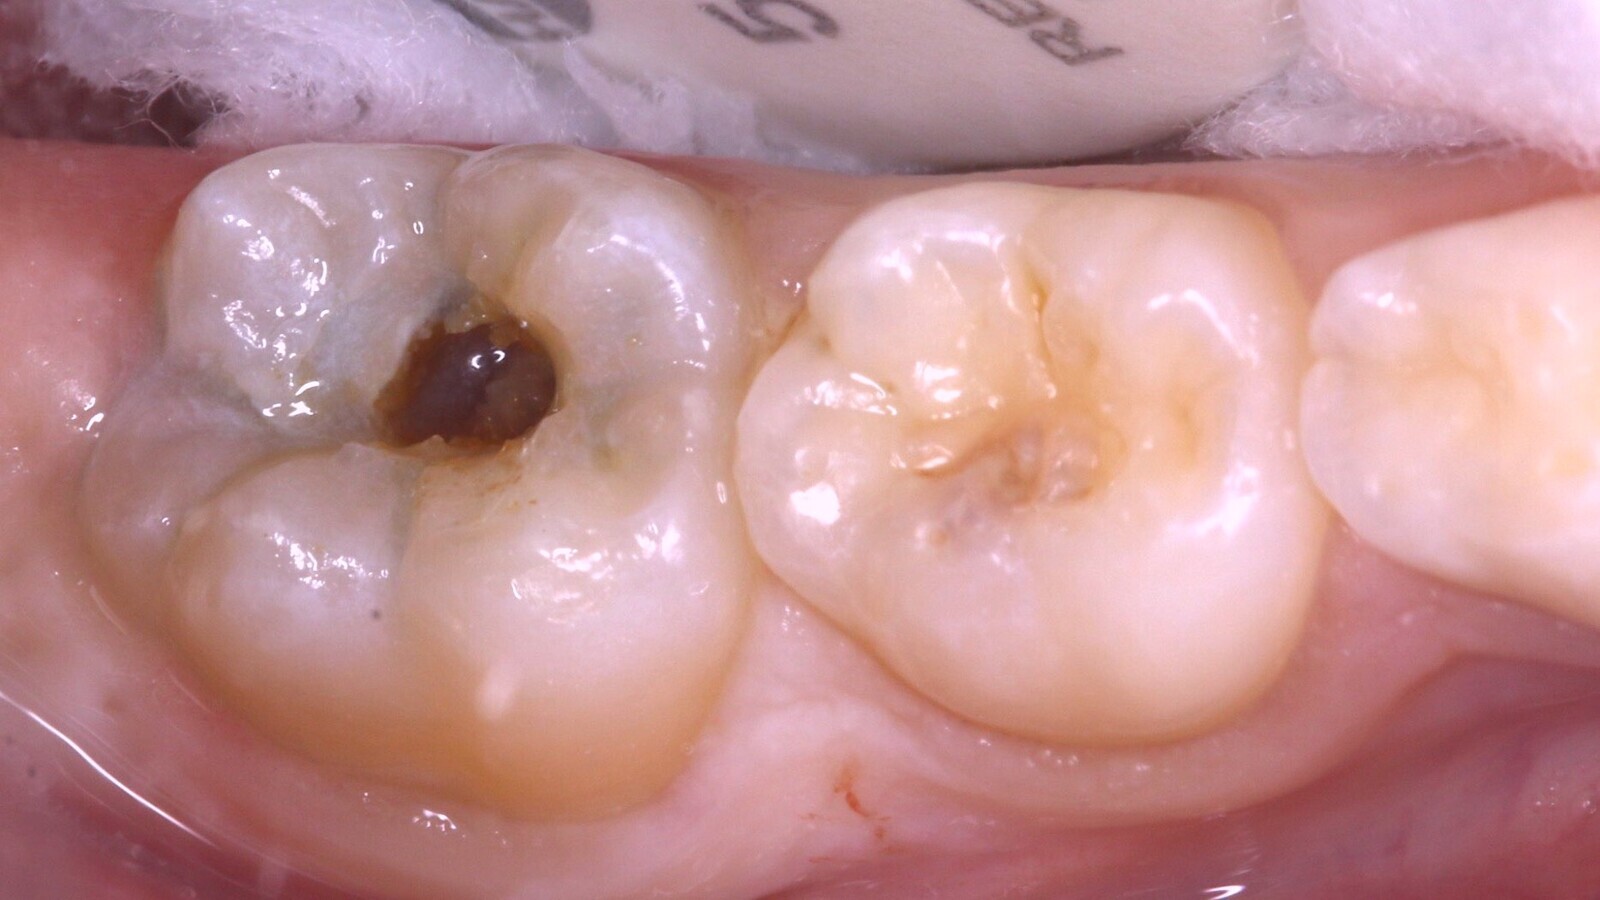

Fig. 1. El diente 46 presenta una sombra subyacente en la dentina apreciada desde oclusal.

Al realizar el examen clínico, el diente 46 presenta una sombra subyacente en la dentina apreciada desde oclusal (Fig. 1), que al manejar el sistema internacional de detección y valoración de caries dental se considera una lesión ICDAS 4 (sombra subyacente en la dentina con esmalte aparentemente intacto). El examen radiográfico, con una exposición de aleta de mordida, evidencia una imagen radiolúcida que alcanza al tercio medio de la dentina (Fig. 2).